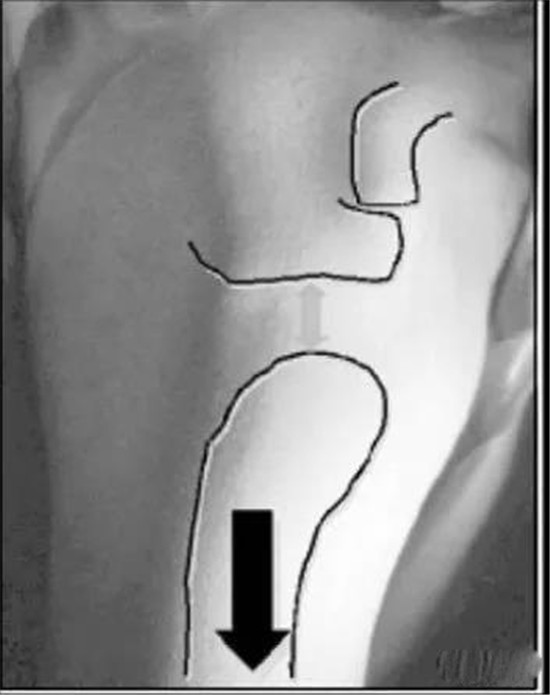

4.下方不稳:

沟槽征( Sulcus sign ):患者坐位,放松肩部肌肉,检查者一手固定肩胛骨,一手在患者肘部施加向下的力,如果肩峰下出现横沟,>2cm者为阳性。阳性结果说明下方不稳,一般均有多向性不稳存在。10月19日黑龙江站中医小儿推拿保健师培训班--点击查看